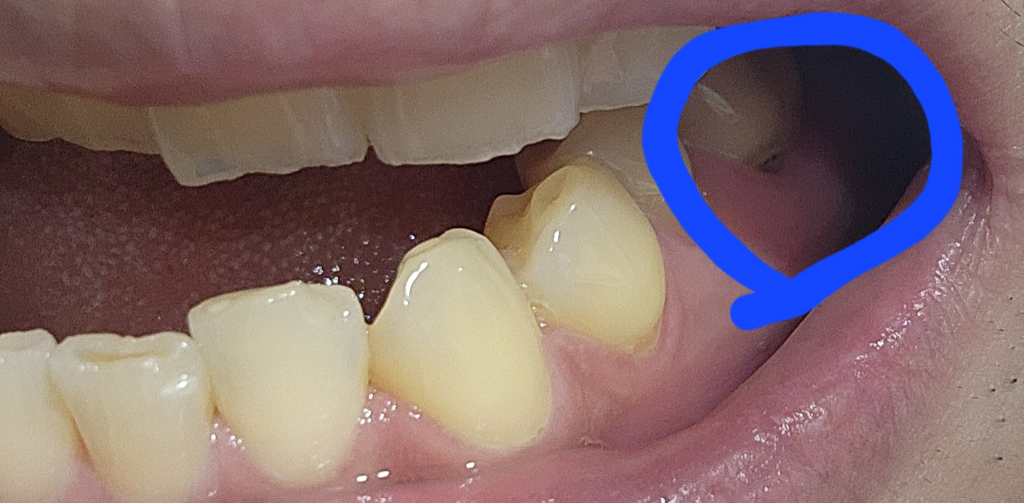

해당 부가 검게 보인다면 해당 부위에 충치가 있을 가능성이 높습니다.

이런 경우엔 충치를 제거하고 치과형 재료로 충전을 해주는 것이 좋을 수 있습니다. 자자 확인을 위해서 치과에서 진료를 받아보는 것을 권유드립니다.

사진이 어두워서 정확하기 알지는 못하겠습니다. 치아 뿌리쪽에 충치가 생겼을 수 있습니다.

현재로선 사진으로만 봐서는 충치로 생각됩니다 잇몸하방으로 충치는 좀 더 깊게 진행되어 있을 수도 있습니다 스케일링과 연관 된다기보다는 원래 충치가 있었고 치석 등에 가려져 있다가 스케일링 후 드러난 것이 아닐까 추측됩니다

저부위는 잇몸이 내려가면서 치아의 뿌리가 노출된 치경부 마모상태이신거 같은데 충치가 잇는거 같습니다 .